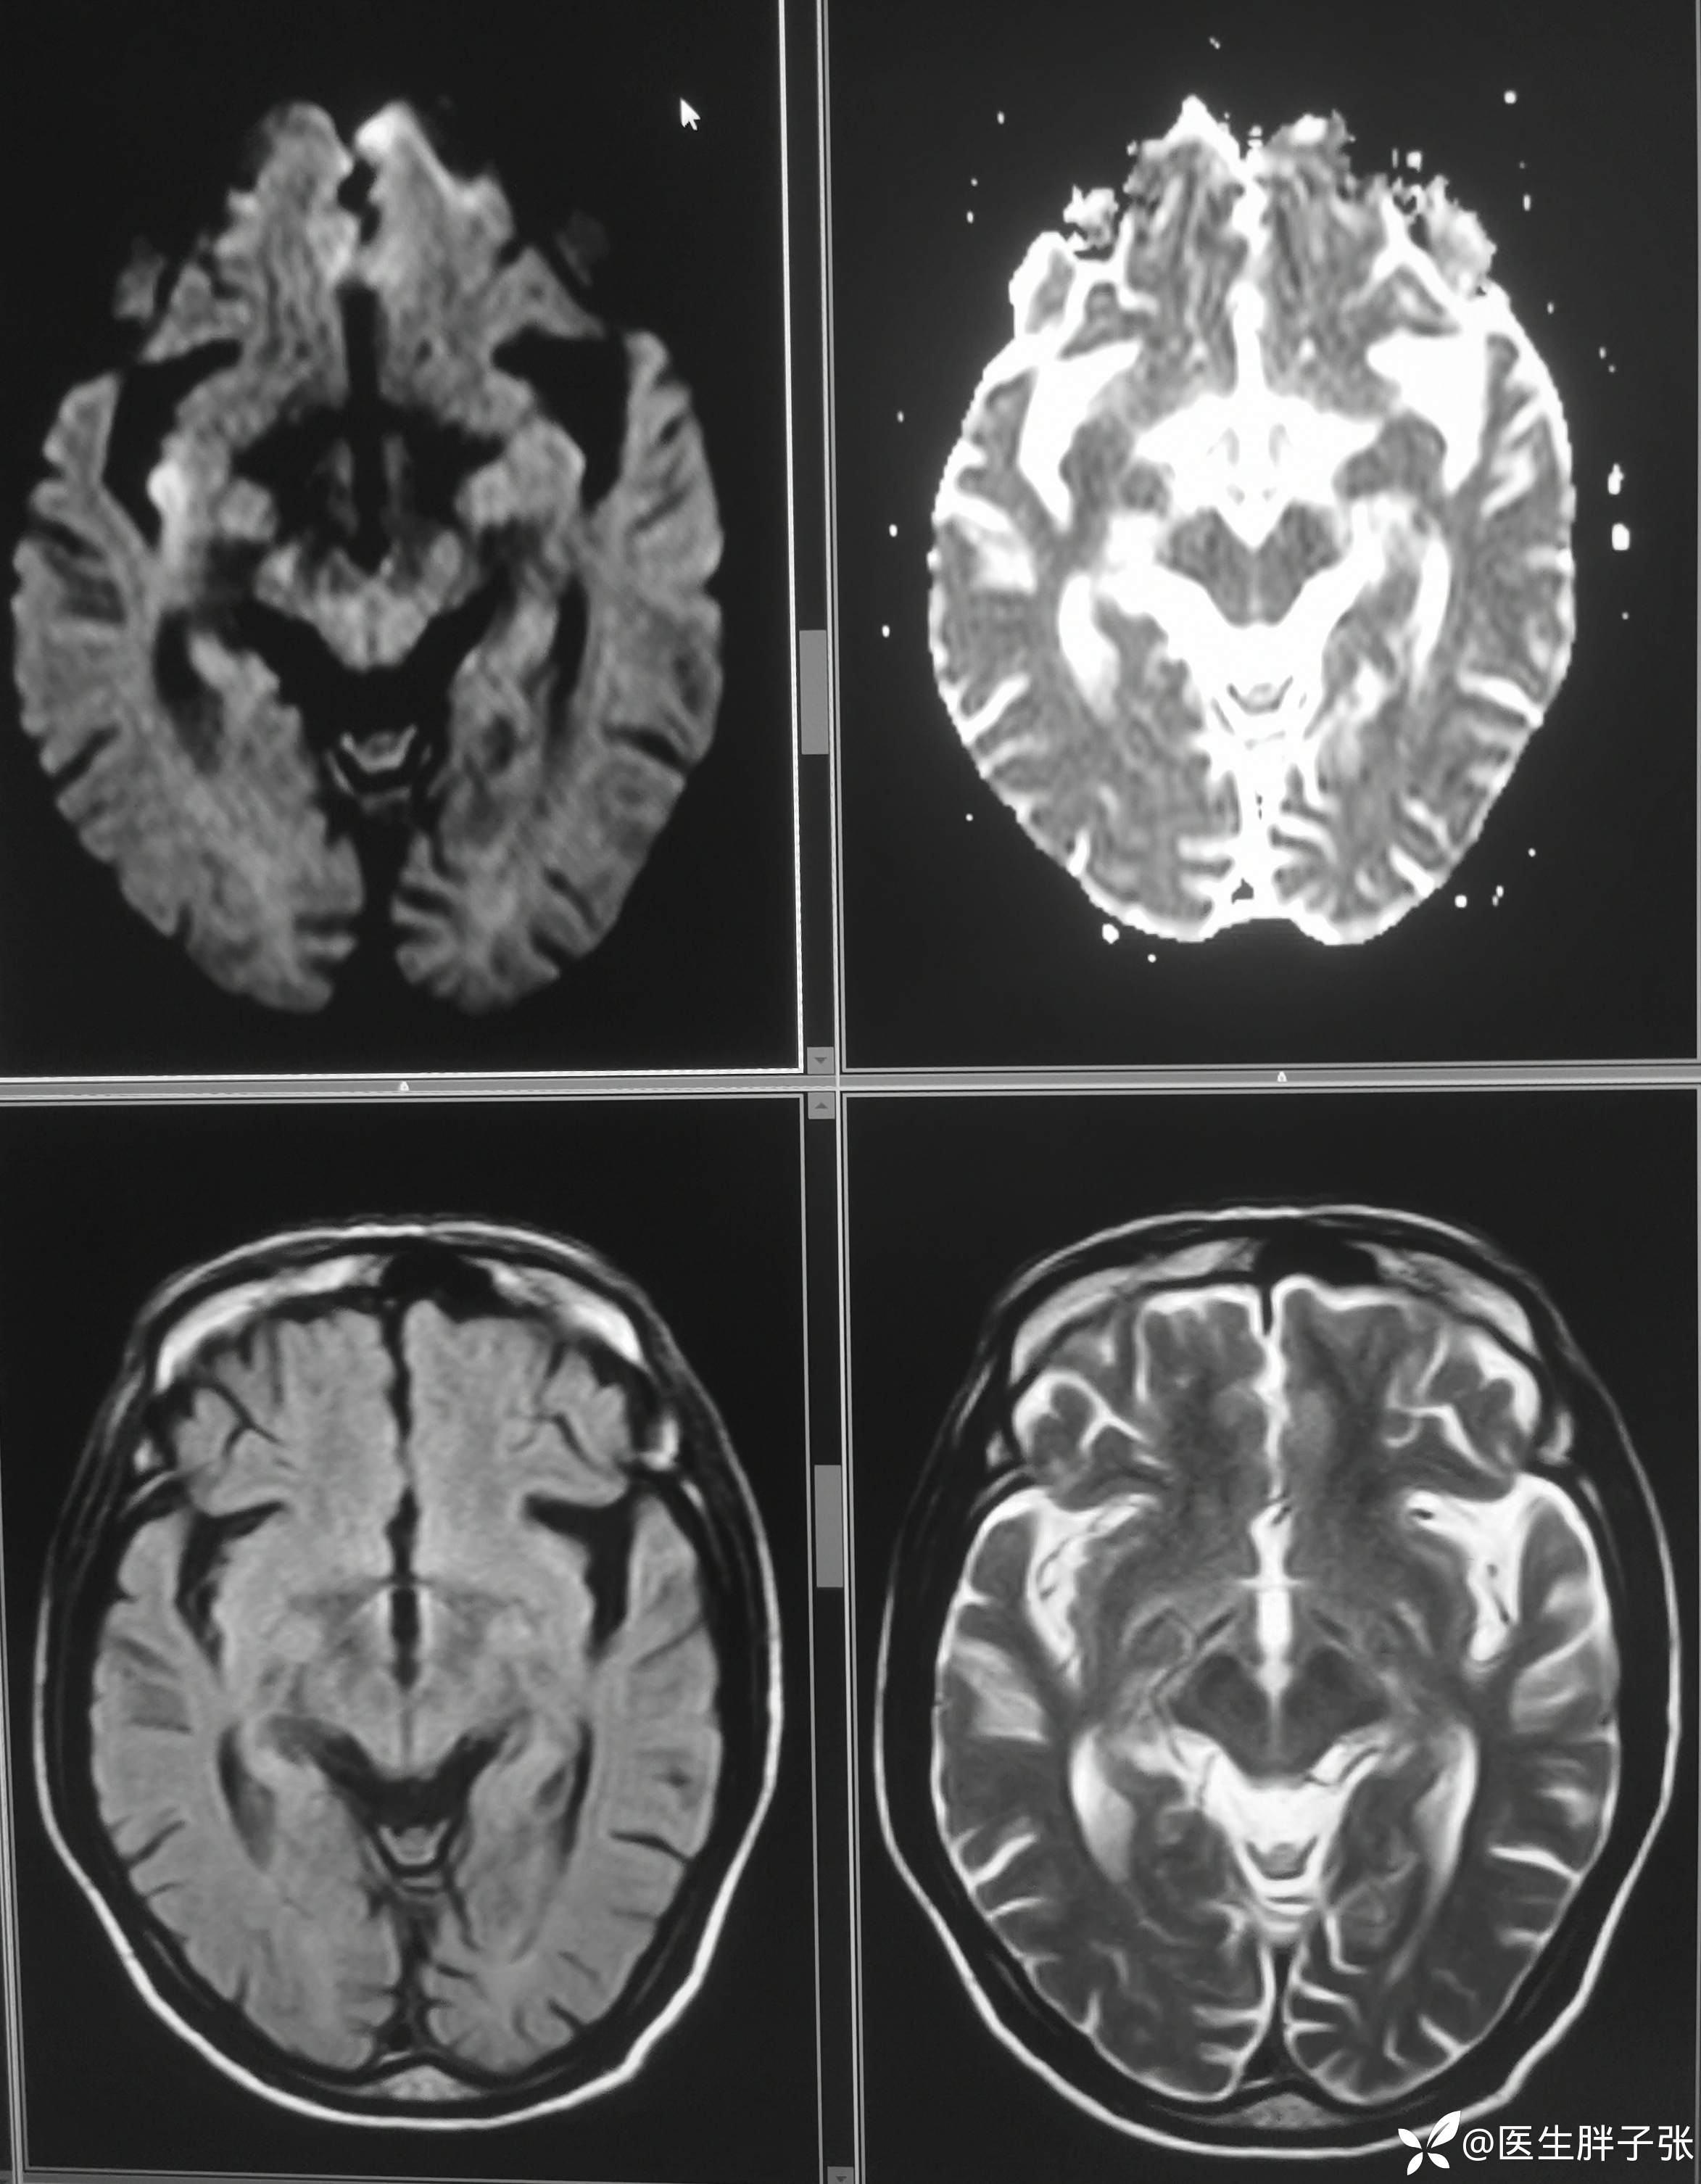

颅脑MR:右侧颞叶新近梗死灶;老年性脑改变;右侧大脑中动脉部分M2段及以远未见显示,建议头颈部CTA检查。

患者为醒后卒中患者,幸运的是恰好晨起交班的时候来院,恰好能查核磁,核磁提示存在DWI-FLAIR错配

溶栓过程顺利,无并发症。患者发病前有腹泻,MRA提示右侧大脑中M2闭塞可能